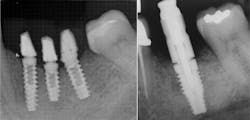

Importance of radiographs

Component mating is critical with implant prosthetics. As the connection is subgingival, it is difficult to visualize how well the prosthetic will connect to the implant connector. Bone or soft tissue may hamper full seating, or the abutment may be rotated slightly so that it and the implant connector do not ideally align. Tightening the fixation screw may provide the perception that the parts are mated, when radiographically they are not. It is also important to radiographicallyConclusion